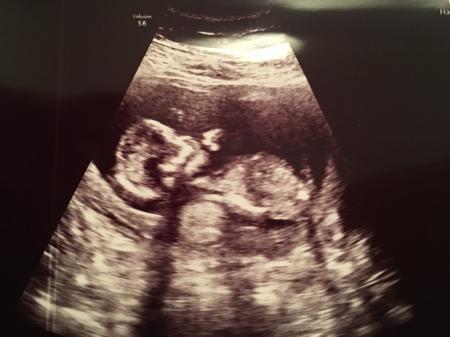

Huhu, auch ich bin vom Termin zurück. Hatte ihn heute leider sehr spät, dass nächste mal dann früher. Hatte heute ein US machen lassen und selbst bezahlt da ich einfach so arg krank war, dass ich vor dem Praena Test sicher sein wollte das es dem Wurm auch wirklich gut geht. Und siehe da, es ist als munter hoch und runter gehüpft. So langsam glaube ich es denkt es sei in einer Turnhalle Sonst ist alles zeitgemäß entwickelt und schon stolze 6,5 cm groß Mitte bis Ende nächster Woche wissen wir dann durch den Praena Test ob es gesund ist und auch welches Geschlecht es hat Hach ich bin soooooo verliebt Nächster Termin ist 20.2.17 LG Jacy

Bild zu Hatte auch FA Termin - Forum für August - Mamis

Ach das freut mich riesig für dich . Ich bin auch schon total aufgeregt wegen unserem Test. Es ist auch aufregend so früh das Geschlecht zu erfahren . Und das Bild ist auch super schön!

Aufregend!!!! Wahnsinn. 6,5cm schon. Mensch die kleinen geben gas

Ein kleiner Riese :) wie schön :*

Schön dass alles gut ist und ein schönes Bild hast du